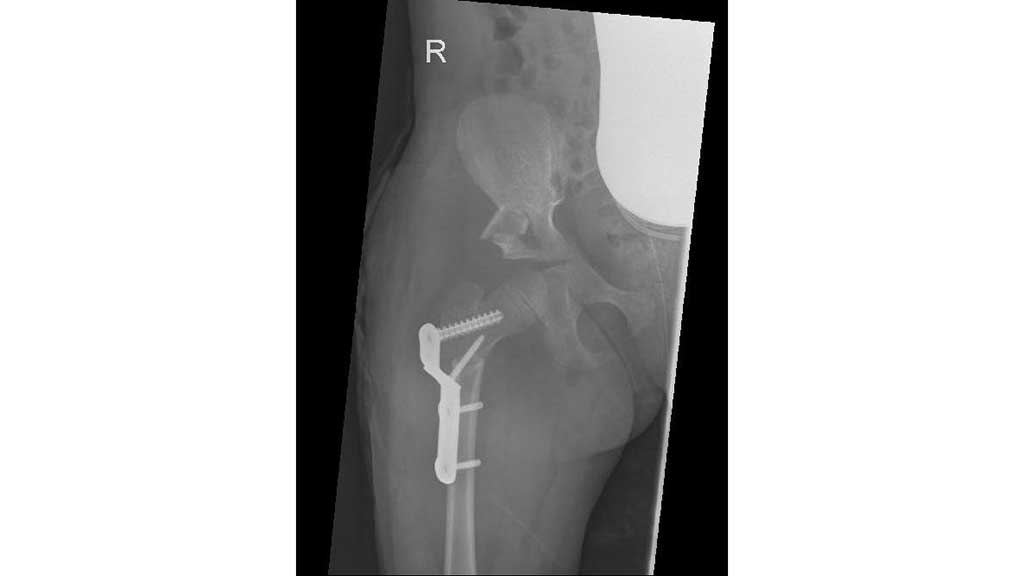

Nach einer ausführlichen Anamnese und der Befunderhebung (ICP, GMFCS V, Frühgeburt 28. SSW) sowie der Röntgendiagnostik steht fest, dass die rechte Hüfte subluxiert ist (Abb. 7).

Im Frühjahr 2012 erfolgte dann die umfangreiche Hüftoperation: Adduktorentenotomie beidseits, Psoas-Tenotomie rechts, offene Reposition und DVO und Pfannendachplastik nach Dega mit Surfixplatte rechts (Abb. 8).